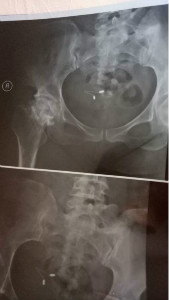

罗丹,骨坏死中心主任,副主任医师。毕业于河南中医学院中医学专业。中华中医药学会青年委员,全国中医临床特色技术传承骨干人才。师从上海名老中医詹红生老师,从事骨伤科诊疗10余年,擅长运用中医辨证思维及手法、针灸等治疗股骨头坏死、月骨坏死、足舟骨坏死、骨梗死、关节滑膜炎、髋关节关节炎、先天性髋臼发育不良。特色:根据患者病情量身制定康复方案,快速指导患者康复。

宋京博,副主任医师/骨关节一科主任。现任中国中医药研究促进会骨伤科分会骨坏死专业委员会委员,河南省中西医结合学会骨坏死专业委员会常务委员,郑州市中医药学会骨坏死专业委员会委员。曾到北京德懿堂中医医学研究院进修学习。上海浮真堂周围神经运动功能解剖学与软组织疼痛徒手治疗临床应用高级研修班学习。弘毅惠中医院管理院现代医院创新管理高级研修班进修学习。擅长运用中医中药及传统疗法治疗成人股骨头坏死、儿童股骨头骺坏死、足距骨坏死、手舟骨坏死等各类骨坏死,髋关节骨关节炎、骨髓水肿综合症、髋关节滑膜炎、强直性脊柱炎、腰椎间盘突出症、风湿病、软组织损伤等疾病。从事临床工作10余年,理论知识扎实,经验丰富。荣获国家发明专利1项,省科技进步奖1项,发表学术论文多篇。

王俊发,副主任医师,骨关节二科主任,毕业于河南中医学院,是全国中医药创新骨干人才培训项目培养对象,河南省中西医结合专业委员会骨坏死专业委员会委员,河南省运动医学委员会委员,中国中医药研究促进委员会经方分会委员,郑州市中医药学会骨坏死专业委员会委员。多次被评为医院优秀员工,从事骨伤科诊疗10余年,擅长运用中医辨证思维及手法、针灸等治疗股骨头坏死,腰椎间盘突出症、肌肉软组织损伤等,善于运用中医药辨证施治各种内伤杂病、骨折外伤等疾病。荣获河南省科技成果奖1项,郑州市专利奖1项。

陈喜凤,副主任医师/骨关节三科主任。毕业于郑州大学,曾多次赴院外进修学习,发表国家级论文多篇,对于中医药辨病辩证综合治疗风湿骨病有着丰富的经验,对于股骨头坏死中早期中医药治疗有深入的研究,重视病症结合,强调风湿骨病治疗的功能与心理康复。擅长治疗股骨头坏死及各类骨坏死、髋关节骨性关节炎、髋关节滑膜炎、致密性骶髂关节炎等。

吕景涛,主治医师,现任骨关节四科副主任。毕业于陕西中医药大学,从事股骨头坏死及风湿病的研究治疗10余年,任河南省中西医结合专业委员会骨坏死专业委员会委员,郑州市中医药学会疼痛专业委员会委员、河南省中西医结合风湿委员会委员,发表论文多篇,2013年曾在河南省中医骨干培训班学习;先后进修于陕西省中医研究院、河南省中医院,从事激素型股骨头坏死的研究(系统性红斑狼疮、类风湿性关节炎、肾病综合征、皮肌炎、垂体瘤等各种激素型股骨头坏死研究)、儿童型股骨头坏死、扁平髋、先天性髋臼发育不良、酒精型股骨头坏死及各种疑难颈椎病、腰椎间盘突出、骨性关节炎等骨病的研究与治疗,有独到的见解与方法,得到患者一直好评和同行的认可!

本中心同时治疗肱骨头坏死、足距骨坏死、手舟骨、月骨、全身多发骨坏死骨、骨梗死等,对于髋关节关节炎、髋关节滑膜炎、骨髓水肿综合征、软组织损伤等疾病疗效显著。